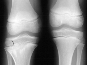

A three year one month old boy presented to AIDI with shortening of the right humerus. Clinical examination revealed 4 cm shortening of right arm and painless limitation of ROM of right shoulder; abduction was 150 degrees with 80 degrees at the glenohumeral joint and internal rotation was significantly limited. There was also 1 cm shortening of the right leg and a 10 degree valgus deformity of the same knee.

Radiological examination showed absence of proximal epiphysis of the right humerus with marked deformity of the metaphyseal region. There was mild shortening of the right tibia in association with destruction of the lateral part of the proximal metaphysis and epiphysis. The diagnosis was neonatal sepsis with multifocal osteomyelitis involving the right humerus and proximal right tibia.

Xrays at age 11 show significant angualtion developed in the humerus . However tibial growth was good .